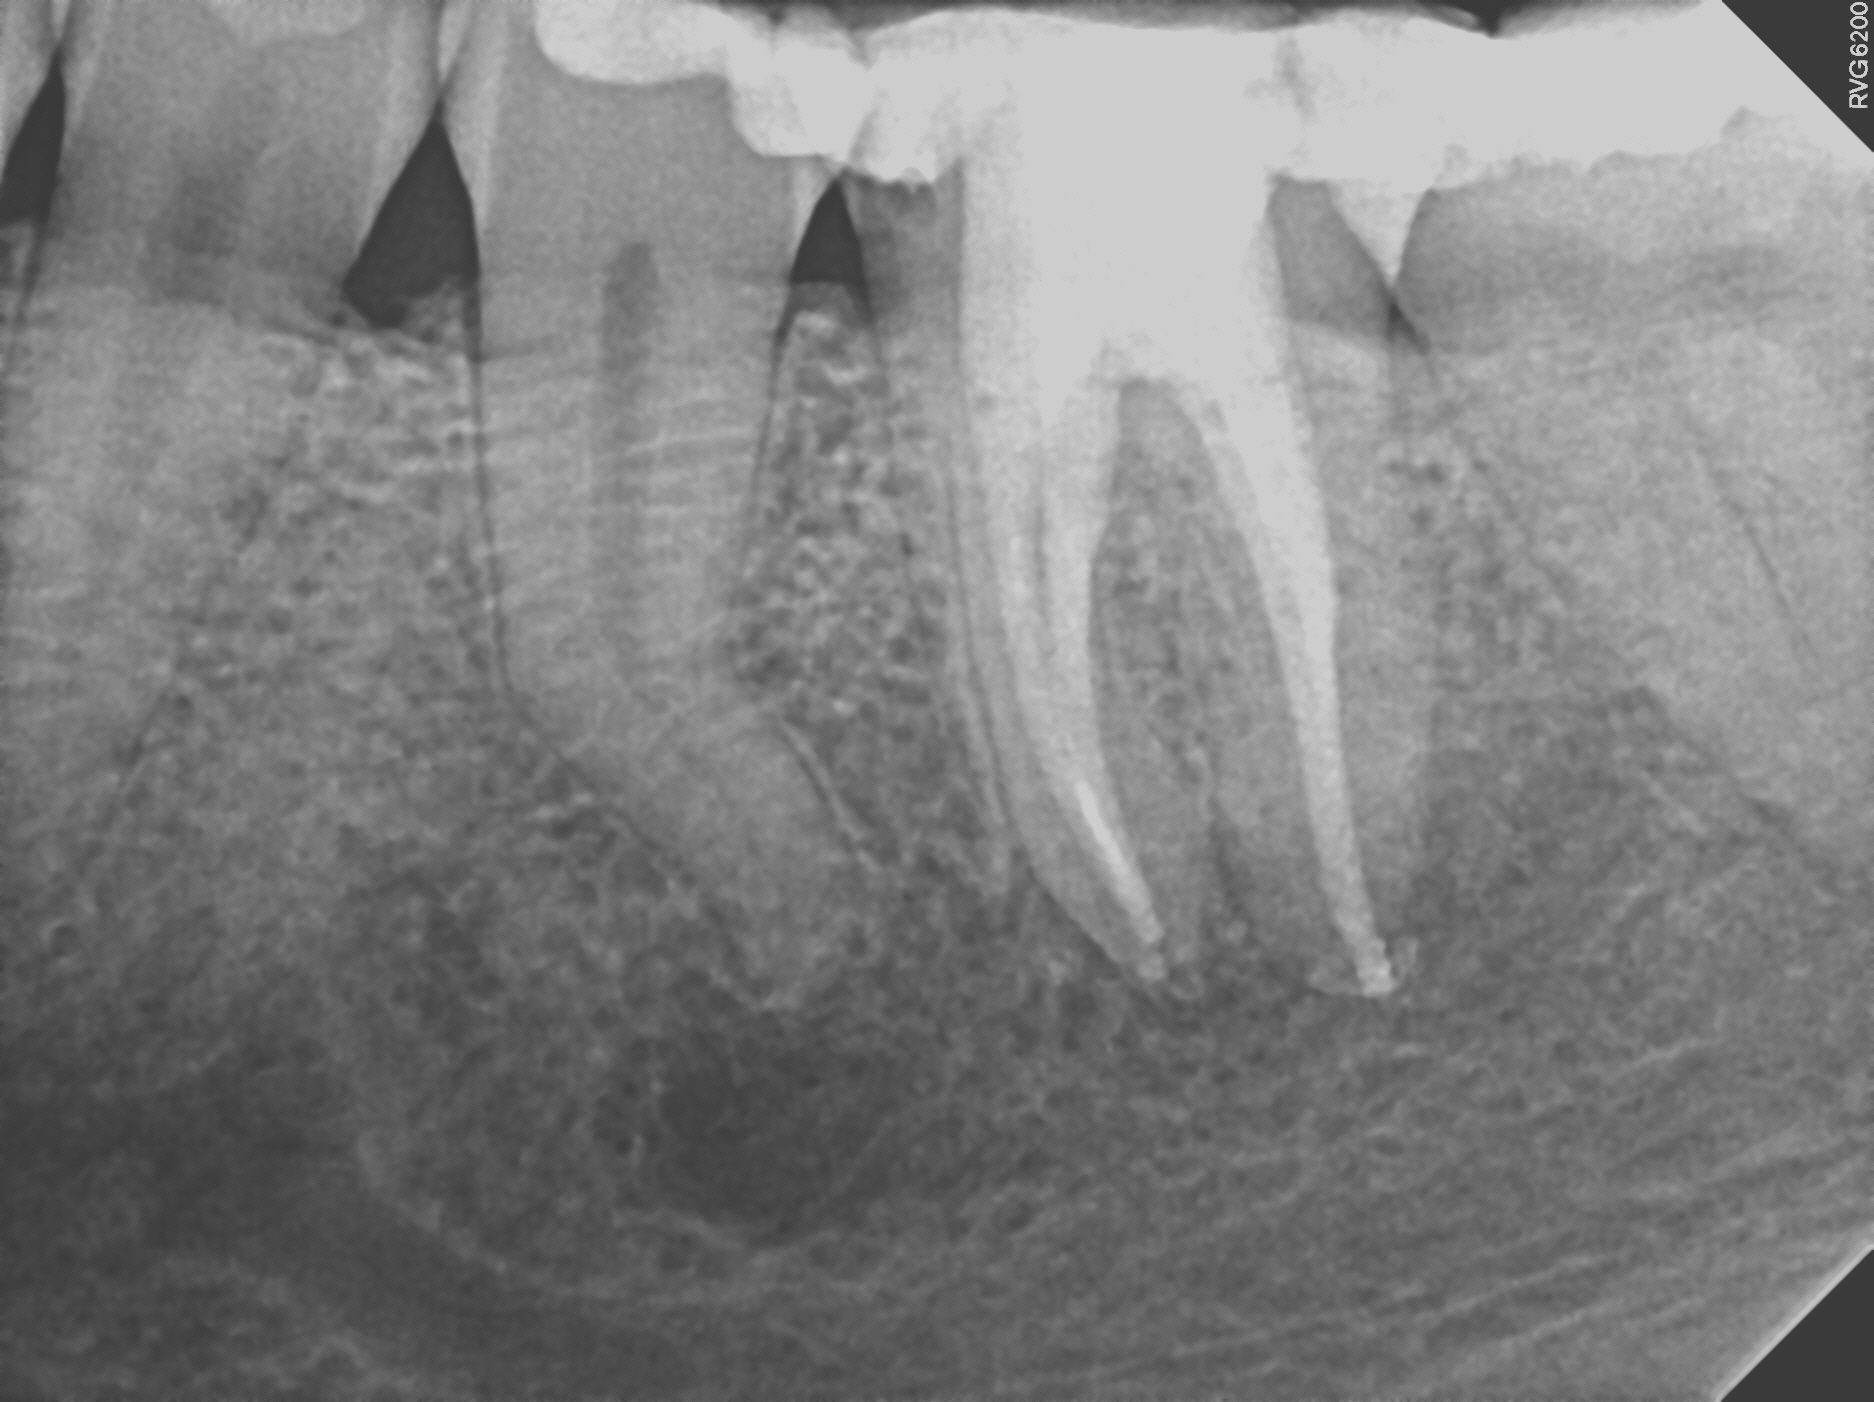

Case 2

This is a retreatment case. The picture on the left shows a lower molar that had been root canal treated many years prior, but either did not heal or at some point afterward became re-infected. The lesion is quite large, extending to the inferior alveolar nerve. While retreating the case Dr Cottle found a previously missed nerve canal (three in one root, five total in this one molar) and was able to disinfect all the canals again. The image on the right shows the completely healed bone one year later.